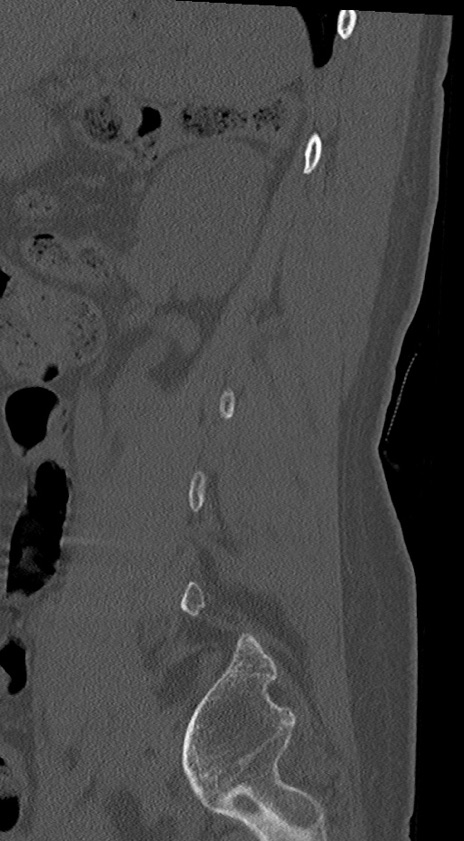

【整形】TIPS症例4 腰椎CT(矢状断像)

腰椎CT

冠状断像